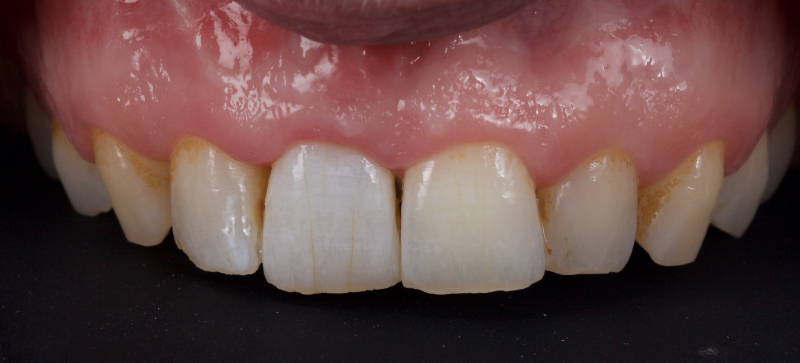

This article explores a more modern, minimally invasive approach to discolored non-vital teeth using the “modified walking bleach” approach. Figure 3 (before treatment) and Figure 4 (after treatment) show an example of this highly conservative approach.